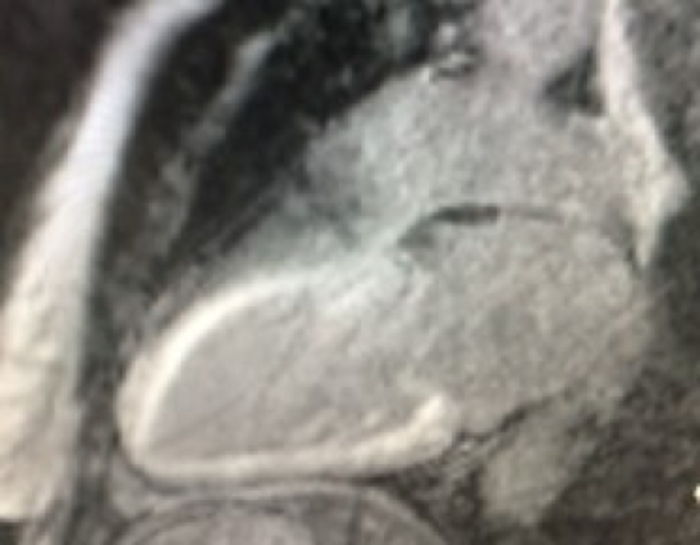

3. Cardiac MRI can be very sensitive for the detection of myocardial infiltration but does not confirm the type of CA